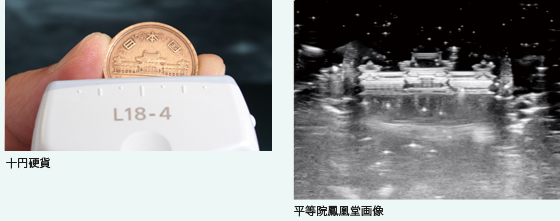

SONIMAGE HS1はこの難関に挑戦し、材料技術と微細加工技術を高度にすり合わせ、高周波では他社に例を見ない広帯域特性を有するプローブの開発に取り組みました。

このプローブ開発によって、直径数百μm程度の筋束や神経束の繊維構造まで鮮明に描出する高画質な画像の提供が可能になりました。

写真開発の技術を活かした高感度化と広帯域化

写真用銀塩フィルム開発で培ったノウハウを生かし、材料設計および合成技術を応用してプローブの根幹となる音響センサー材料の開発を行い、目標とする音響特性を実現しました。

また、プローブ先端部にある音響整合層は、一般的に1~2層で構成されますが、HS1では高度なシミュレーション技術で導き出した理想的な多層整合層構造を、独自開発した材料技術で実現しました。

これにより、高感度化と広帯域化の両立を図り、比帯域幅(帯域幅/中心周波数)100%以上を達成しました。